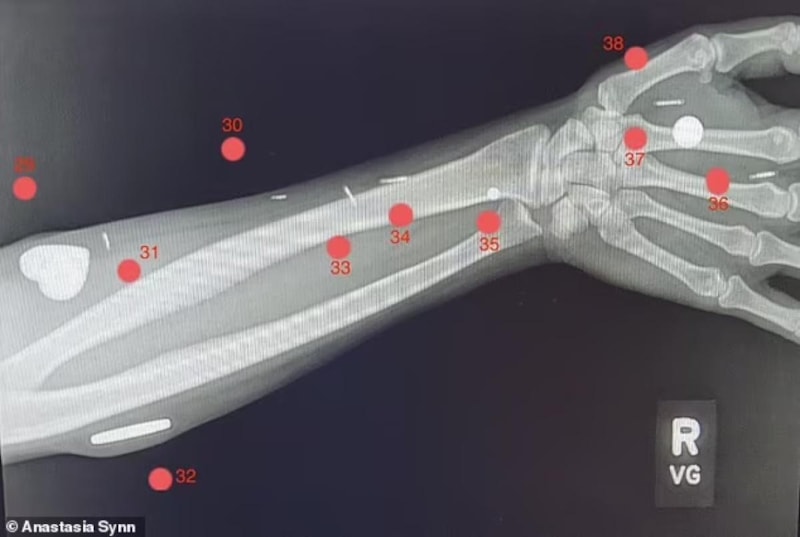

Vücudunda kilitlerini açmasına ve arama yapmasına olanak tanıyan 52 implant bulunan kadın, şimdiden Guinness Rekorlar Kitabı'na girmeyi başardı.

Kaliforniya'da yaşayan 48 yaşındaki Anastasia Synn, vücuduna en teknolojik implantları yerleştiren kadın olarak Guinness Dünya Rekoru'nu elinde tutuyor.

Bu implantlar arasında şimdiye kadar bir insanın içine yerleştirilen en büyük mıknatıs da dahil olmak üzere, kadının vücudunda tam 52 adet çip var.

Anastasia Synn, vücudundaki çipler sayesinde kilitleri ve bilgisayarları rahatlıkla açabiliyor. Çünkü implantlarının yaklaşık yarısı mikroçiplerden oluşuyor.